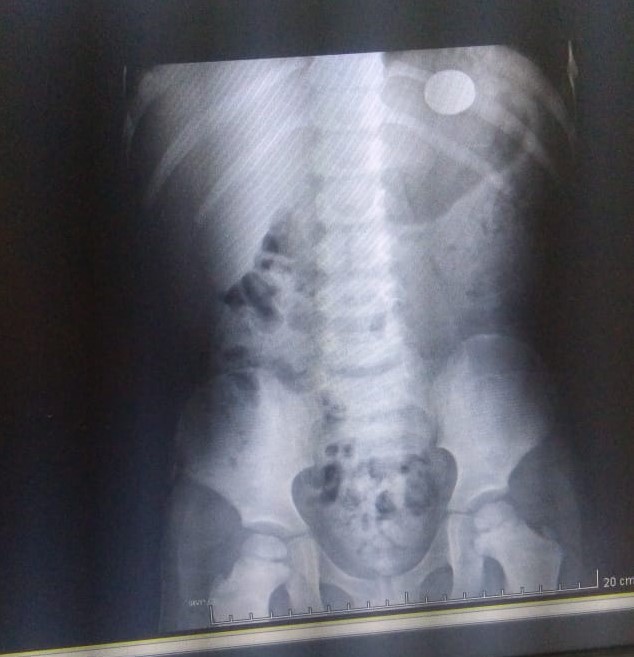

“Ele (o filho) começou a falar que estava com uma dor no coração e então eu perguntei o que tinha acontecido e ai ele contou que teria engolido a moeda e então o levamos à UPA (Unidade de Pronto Atendimento de Ourinhos) e fizemos o exame de raio X e vimos que a moeda estava em sua barriga”, contou a mãe.

O garoto engoliu a moeda no dia 9 (domingo), mas o objeto não se moveu para o intestino e se isso persistir, o menino poderá ter que passar por um procedimento cirúrgico para retirar a moeda.

Imagem da moeda engolida por menino em Ourinhos (Foto: Arquivo Pessoal)